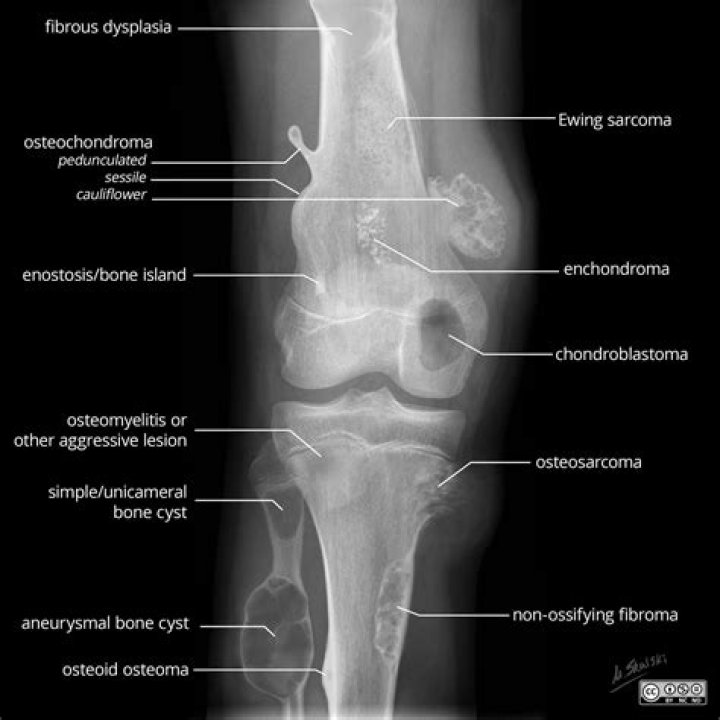

What does osteochondroma look like?

An osteochondroma looks like a bony projection on the external surface of a bone, like a bony mushroom on a stalk, usually near a growth plate area. It can occur in any bone but is seen most often around the knee or upper arm. This tumor generally grows with the child and stops growing once the child completes puberty.

Osteochondroma is an overgrowth of cartilage and bone that happens at the end of the bone near the growth plate. Most often, it affects the long bones in the leg, the pelvis, or the shoulder blade. Osteochondroma is the most common noncancerous bone growth.

An osteochondroma is a cartilage-covered bony excrescence (exostosis) that arises from the surface of a bone. Osteochondromas, which are the most common bone tumors in children, may be solitary or multiple, and they may arise spontaneously or as a result of previous osseous trauma.